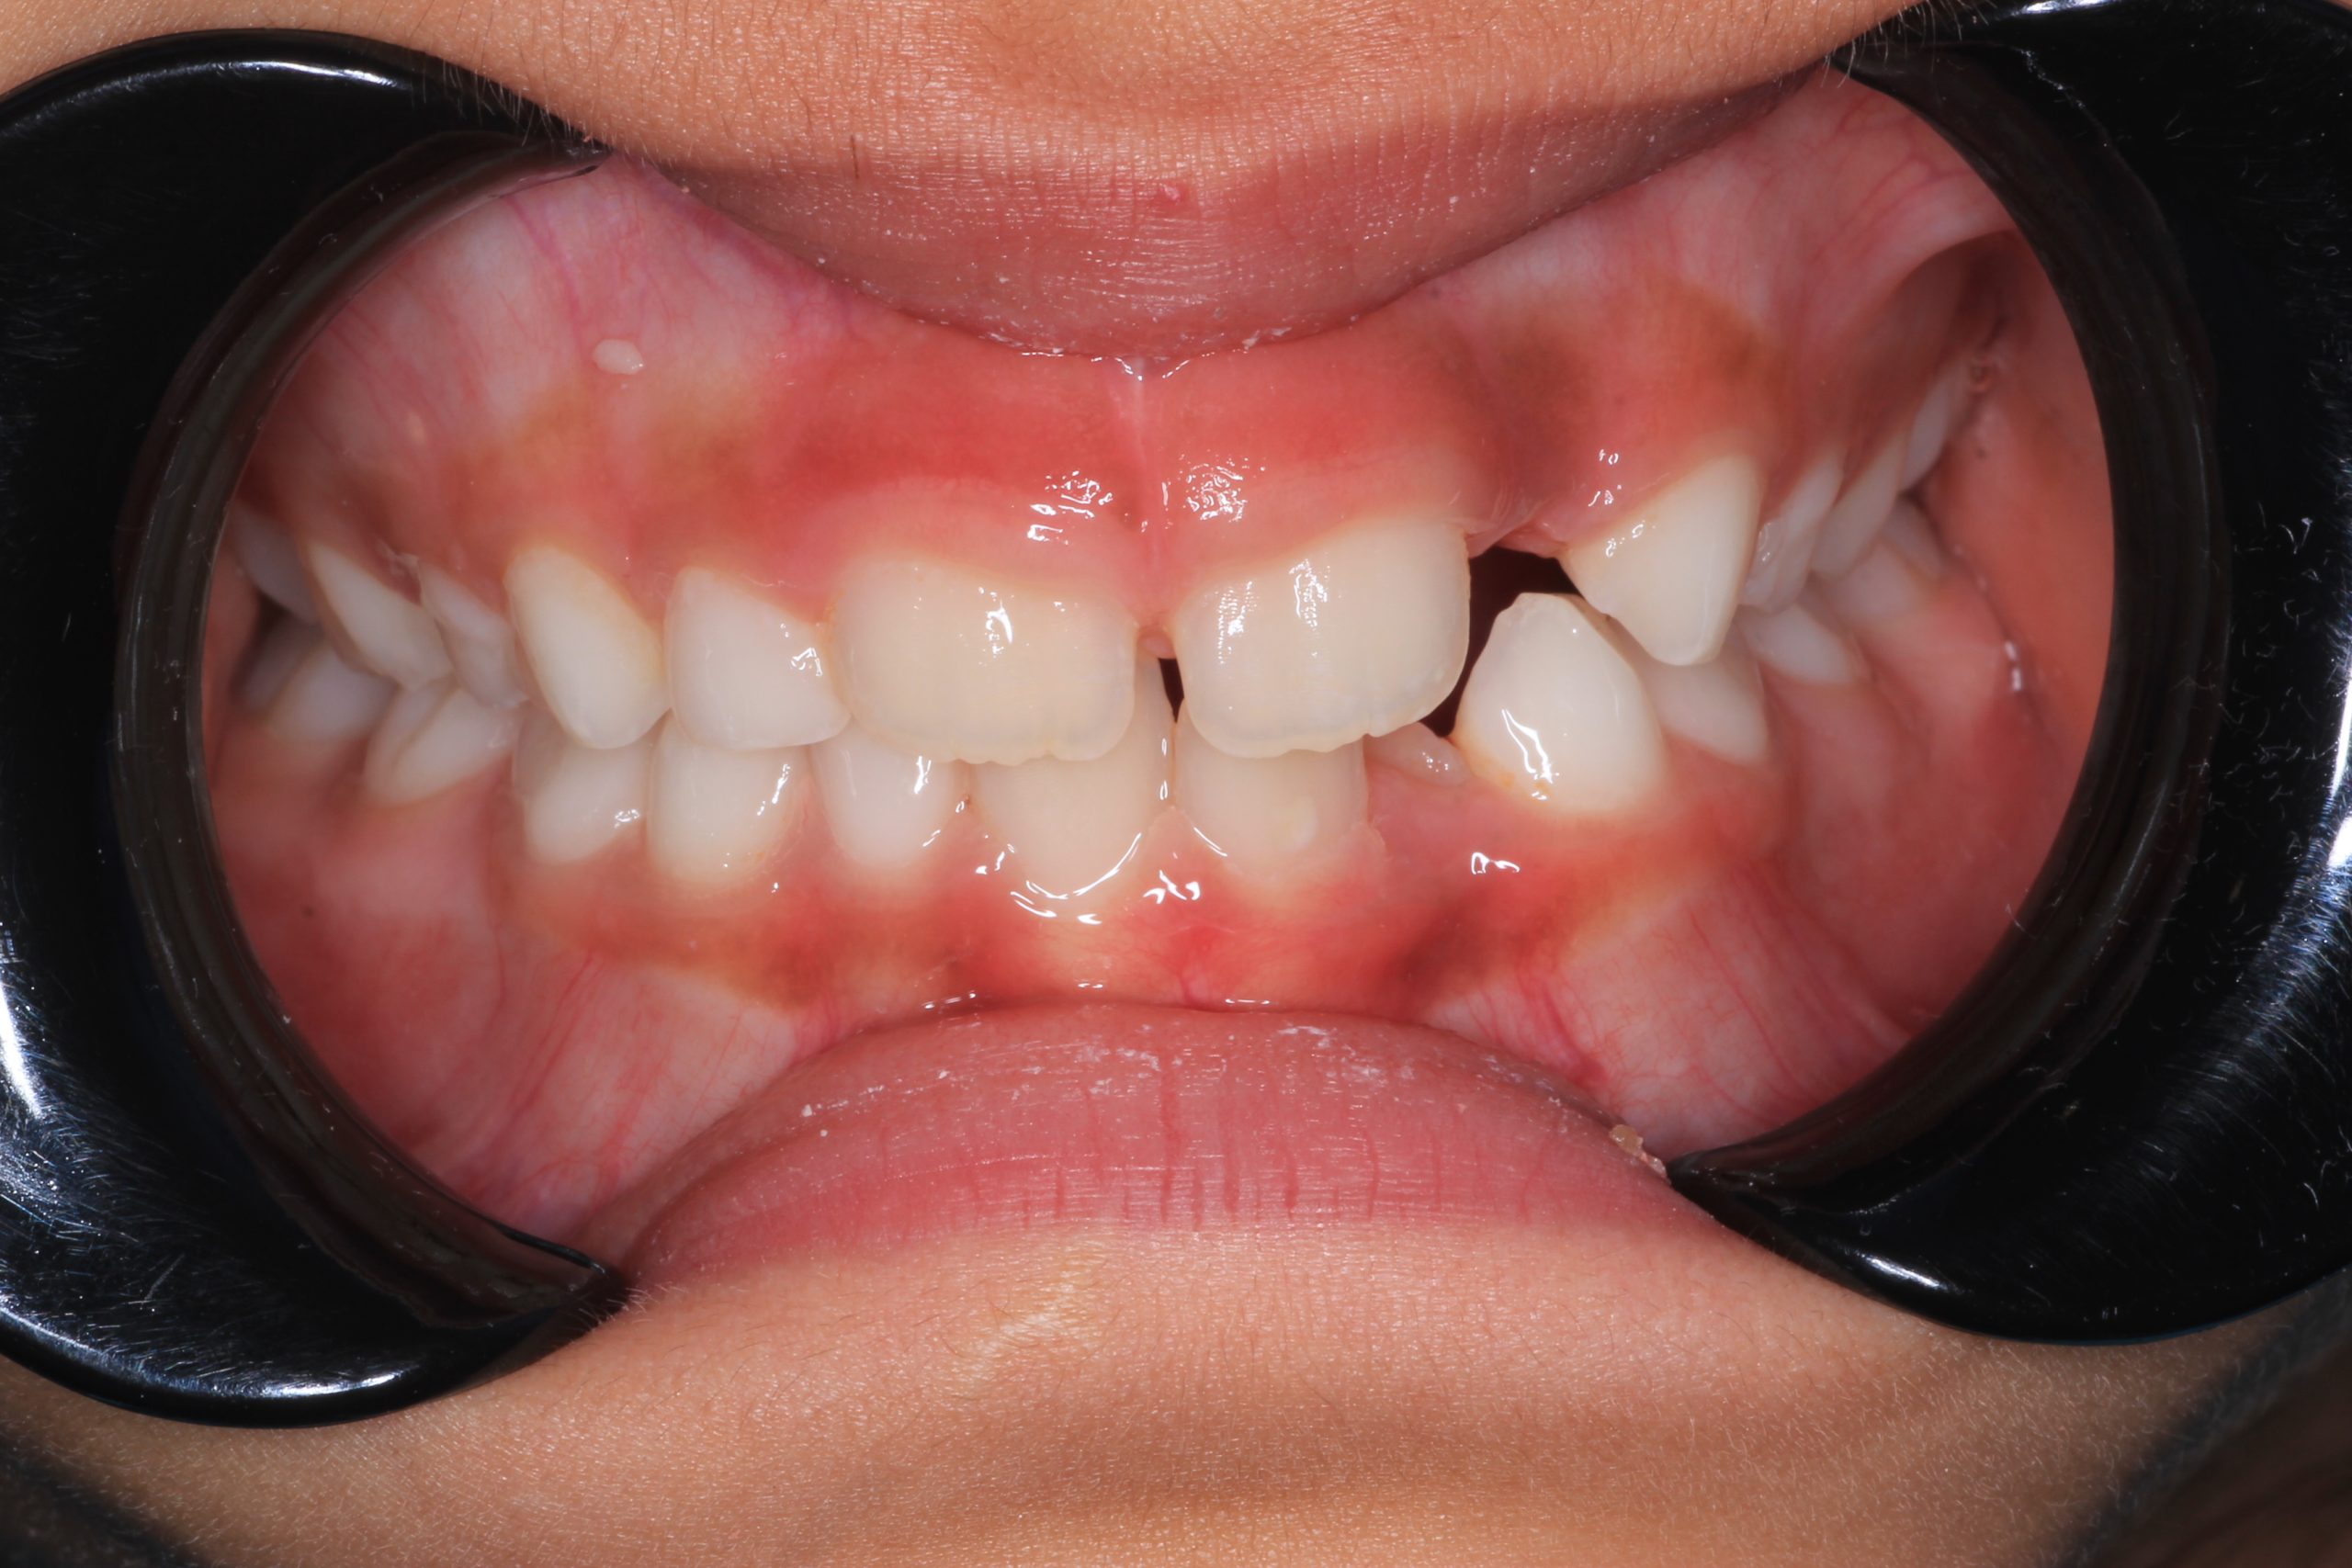

- Detailed Examination

We examine the condition of teeth, gums, and bite. - Plaque Disclosure with Special Indicators